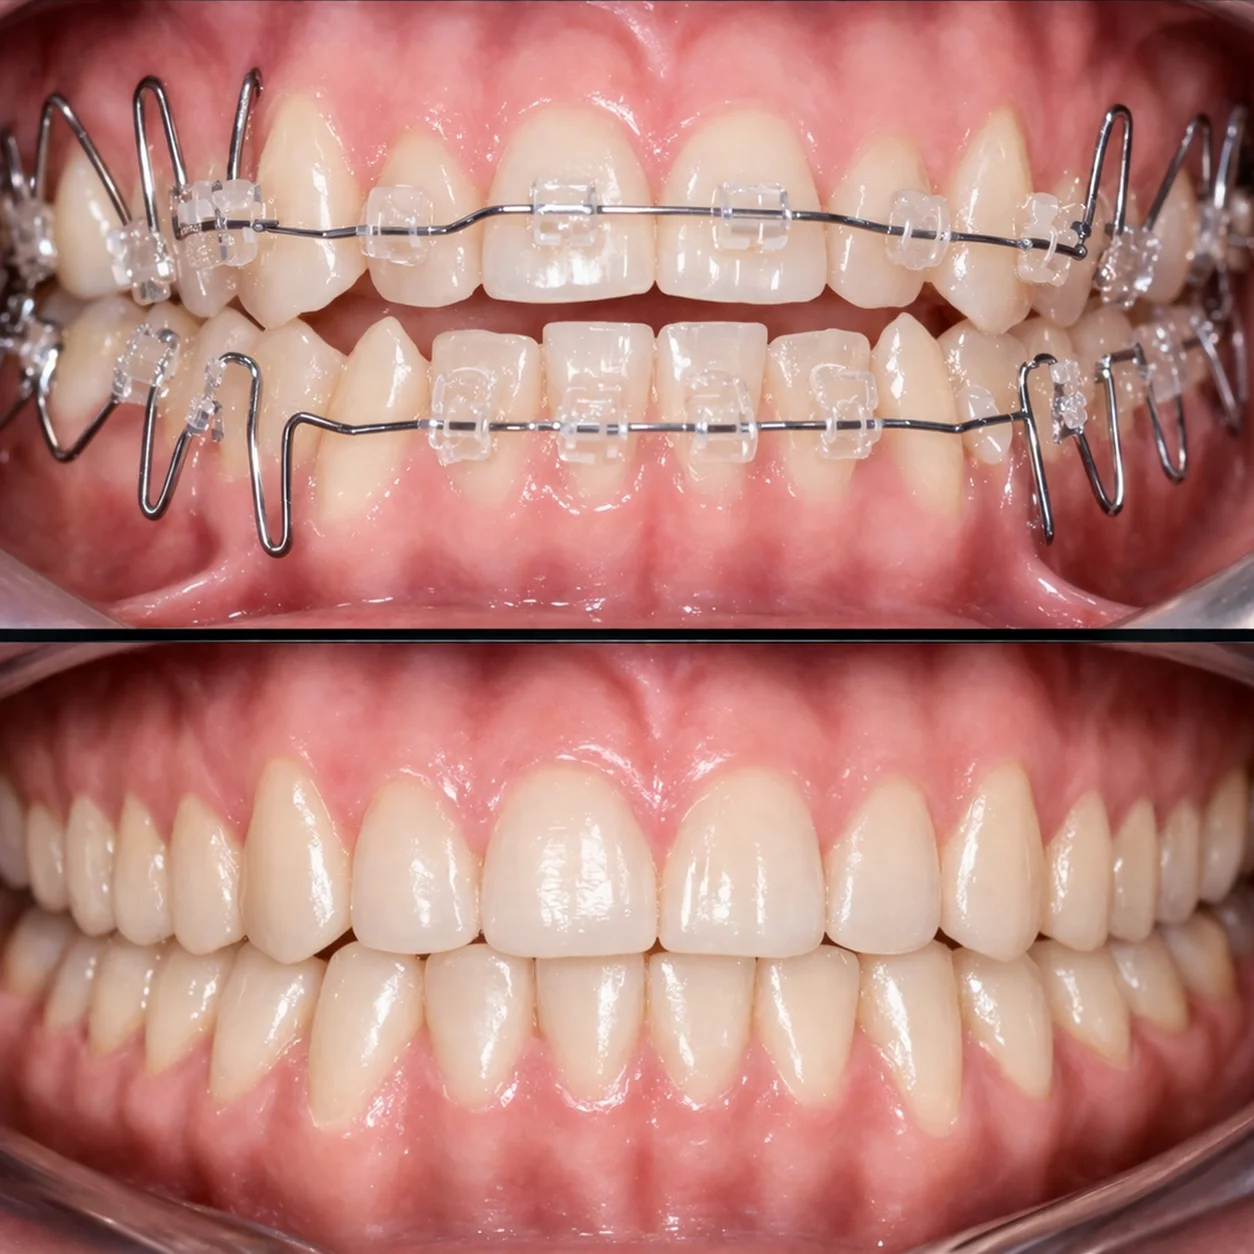

Efekty leczenia

Aparat ortodontyczny

Sięgamy po nie wtedy, gdy potrzebne są poważniejsze zmiany — praca ze zgryzem, stawem i całym układem. Jeśli masz dyskomfort, trzaski w stawie, napięcie mięśni, bóle głowy albo uszu, takie przypadki najlepiej rozwiązywać aparatem